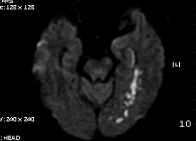

2011-9-10 근력이 G4-  로 지속, 더 이상 나빠지지는 않음. 우측 상지의 움직임이 주과적으로 둔해졌다고 하나 객관적 근력은 정상입니다. Diffusion만 촬영하였습니다.

# 손 o 일 교수님 의견

DWI coronal or saggital view 보면 분명하겠지만 이 사진으로 보니 PCA territory infarction으로 모두 설명되는 것 같습니다. PCA 영역에 hypoperfusion으로 병변이 크지는 것 같습니다. 5-7일 지나야 안정기에 들어갈 것 같습니다.